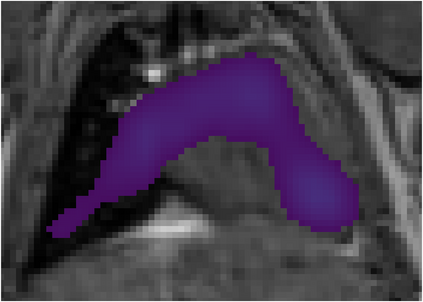

Various imaging modalities allow for time-dependent image reconstructions from measurements where its acquisition also has a time-dependent nature. Magnetic particle imaging (MPI) falls into this class of imaging modalities and it thus also provides a dynamic inverse problem. Without proper consideration of the dynamic behavior, motion artifacts in the reconstruction become an issue. More sophisticated methods need to be developed and applied to the reconstruction of the time-dependent sequences of images. In this context, we investigate the incorporation of motion priors in terms of certain flow-parameter-dependent PDEs in the reconstruction process of time-dependent 3D images in magnetic particle imaging. The present work comprises the method development for a general 3D+time setting for time-dependent linear forward operators, analytical investigation of necessary properties in the MPI forward operator, modeling aspects in dynamic MPI, and extensive numerical experiments on 3D+time imaging including simulated data as well as measurements from a rotation phantom and in-vivo data from a mouse.